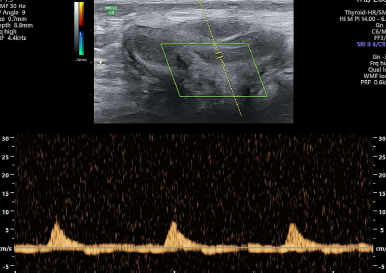

Penile Color Doppler available in # Rohini # Pitampura A penile doppler ultrasound is a minimally invasive imaging technique that uses high-frequency sound waves to create images of the inside of the body and map blood flow in the penis. It's a useful tool for diagnosing erectile dysfunction (ED) and other penile conditions.